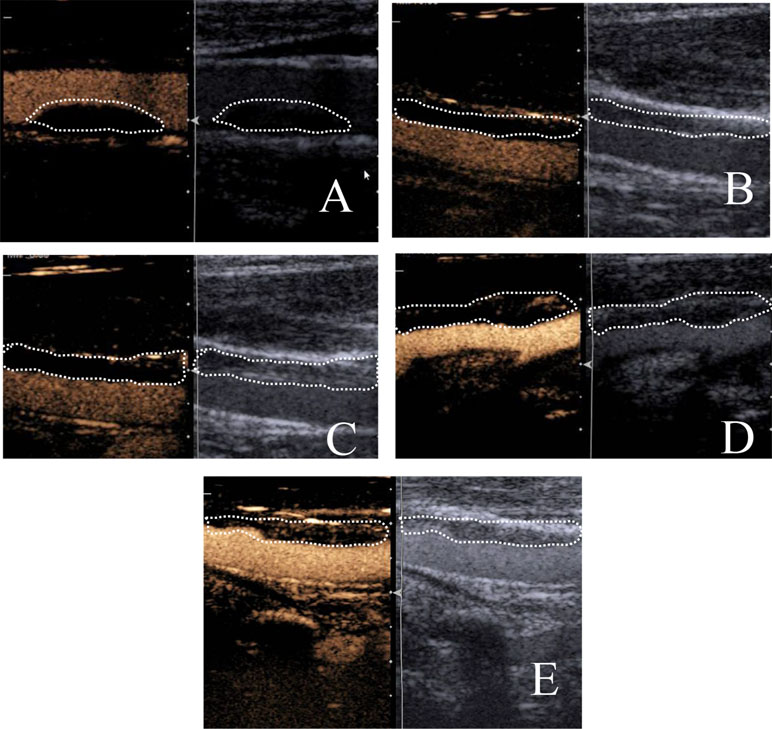

Measurements of carotid plaque and intimal-medial thickness (IMT) using …

Carotid Artery Thickness..

Frontiers | Prospective Study About the Relationship Between CEUS of …